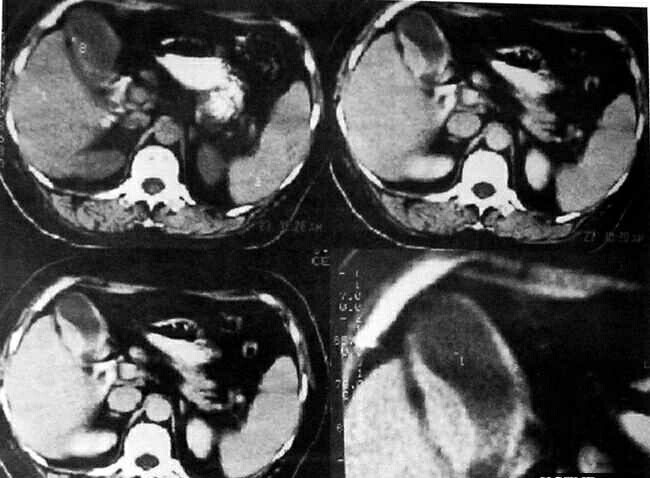

【病史】女性,64岁,反复右上腹不适半年余。体检:右上腹压痛。 【影像】CT平扫:胆囊大小形态基本正常,胆囊壁局限性梭形增厚,增强扫描:病灶强化明显,胆囊腔内面较光整。胆囊周围境界尚清晰,邻近肝组织未见明显累及。胆管不扩张。诊断:胆囊癌可能性大(胆囊壁增厚肿块型)。 【最后诊断】病理诊断:增生性胆囊炎。 【点评】术前误诊为胆囊癌,主要基于患者年龄64岁,胆囊壁局限性肿块样增厚,且明显强化,酷似肿块型胆囊癌。但仔细分析,以下几点值得今后注意: 1.胆囊壁增厚是胆囊炎的重要诊断依据,胆囊壁增厚常呈弥漫性、向心性,但少数病人增厚的胆囊壁呈结节状,与胆囊癌表现相似。增厚的胆囊壁增强扫描时也呈明显强化,且持续时间长。其中气肿性胆囊炎的胆囊壁内可显示气泡或线状气体影,出血性胆囊炎除胆囊壁增厚和胆囊内结石外,胆囊内的血性内容物密度较高,钙胆汁的密度通常更高; 2.胆囊癌分为胆囊壁增厚型、腔内型和肿块型。胆囊癌和胆囊炎均可表现为胆囊壁增厚,一般认为以下征象可作为胆囊癌诊断的参考。(1)胆囊壁不均匀特别是结节状增厚;(2)胆囊壁增强明显;(3)出现胆管梗阻;(4)直接侵犯肝脏或肝内出现转移灶。而下列征象支持胆囊炎的诊断:(1)胆囊囊周围境界清晰的低密度影,反映了胆囊壁的水肿或胆囊炎所致胆囊周围的液体渗出;(2)胆囊壁增厚而腔内面光整。